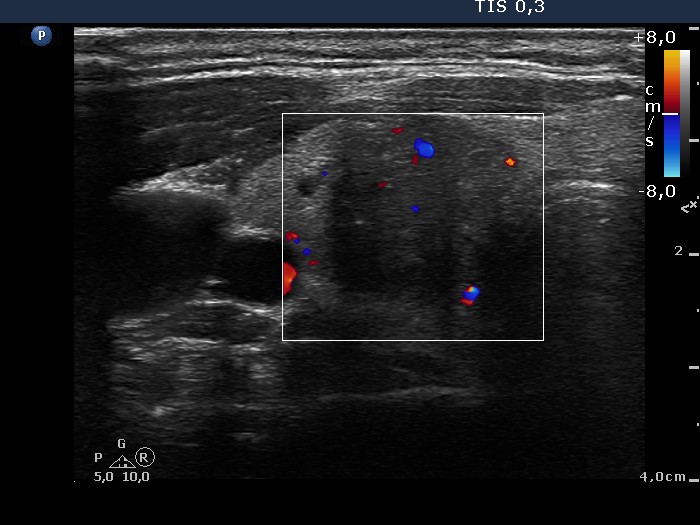

The borders of the nodule - case conp 053 (ultrasonographic picture 5)

Right lobe, transverse scan, color Doppler mode. The nodule presents signs of intranodular blood flow.